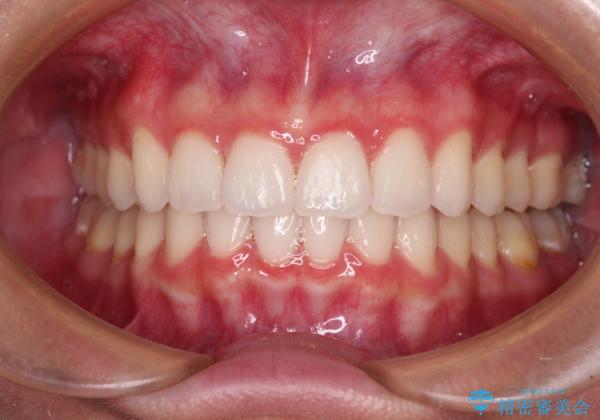

歯と歯の間を削ることで、飛び出した前歯が引っ込み、スッキリとした口元となりました。

歯の黄ばみも改善され、明るい歯並びとなりました。